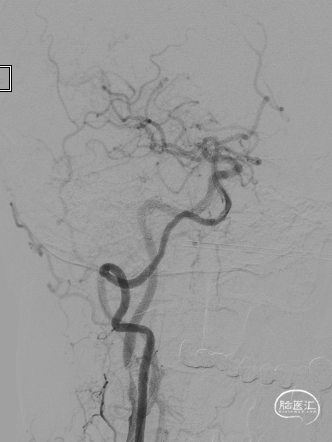

长SIM与6F导引导管同轴,泥鳅导丝引导下将6F导引导管送至颈总动脉远端(左图),保护伞到位(右图)。

4.0*30mm通桥白驹®球囊以6atm扩张(左图箭头),扩张完毕后多角度造影显示狭窄交前明显改善(中图箭头处),扩张完毕后支架置入(右图箭头处)。